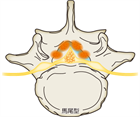

1. 馬尾型もしくは混合型の腰部脊柱管狭窄(LSS)による間欠跛行患者にはリマプロスト投与を推奨する(推奨度2)